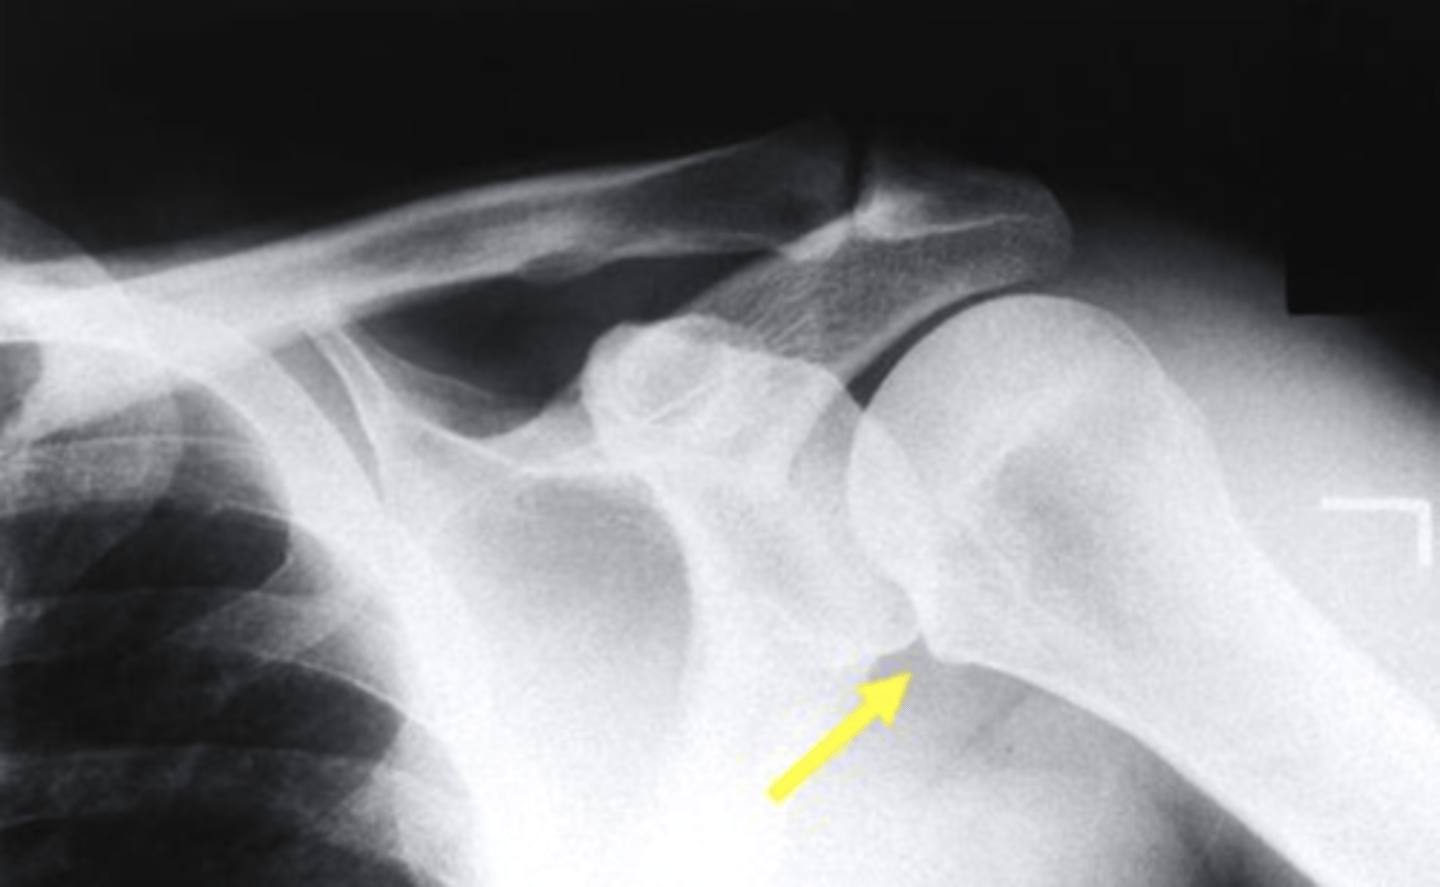

Which structure is highlighted by the yellow arrow in this AP view of the shoulder with internal rotation?

lesser tuberosity